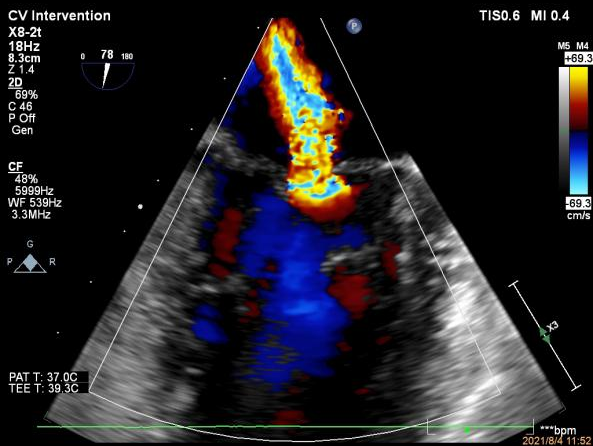

患者术前TEE提示重度功能性二尖瓣反流,反流位于A2/P2,瓣膜活动度可,后瓣较短,手术难度较高(图1)。手术采用经典股静脉房间隔途径,房间隔穿刺后植入24F导引导管及二尖瓣夹输送系统,在TEE引导下准确植入一枚二尖瓣夹,瓣膜夹位置稳定。瓣膜夹植入后反流明显减轻至轻度(图2),二尖瓣跨瓣平均压力阶差2mmHg,双孔化形成,遂移除输送系统。

图1:术前TEE提示重度二尖瓣反流